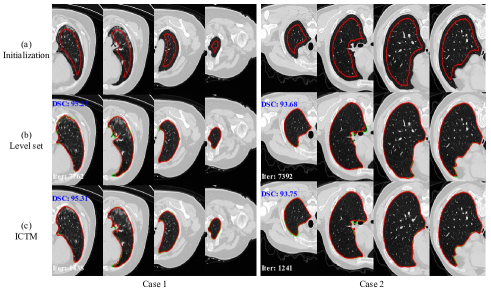

4.3 Lung segmentation in COVID-19 CT

For fair comparison, we apply the grid search to tune the hyper-parameters, which aims to achieve the best performance for both LSM and ICTM. Quantitative and qualitative segmentation results are displayed in Table 2 and Figure 3, respectively. We observe that both two methods achieve comparable average DSC without significant differences, which implies that the ICTM can be an alternative choice (beyond the LSM) for the GAC. The average iterations of ICTM is 1384, which is 3.86 ×\times lower than the LSM. As for the efficiency, the LSM spends averagely 1956.6 seconds for each case while the ICTM only needs 69.2 seconds, which achieves about 28.328.328.3 times acceleration.

Refer to caption

Figure 3: Zoomed examples for lung CT segmentation results. Row (a) : input images and corresponding initialization (red rectangles). Row (b) : segmentation results of the LSM. Row (c) : segmentation results of the proposed ICTM. Green and red contours denote ground truths and segmentation results, respectively. Blue and white numbers at the top of images point out segmentation accuracy (DSC) and the number of iterations. See Section 4.3.